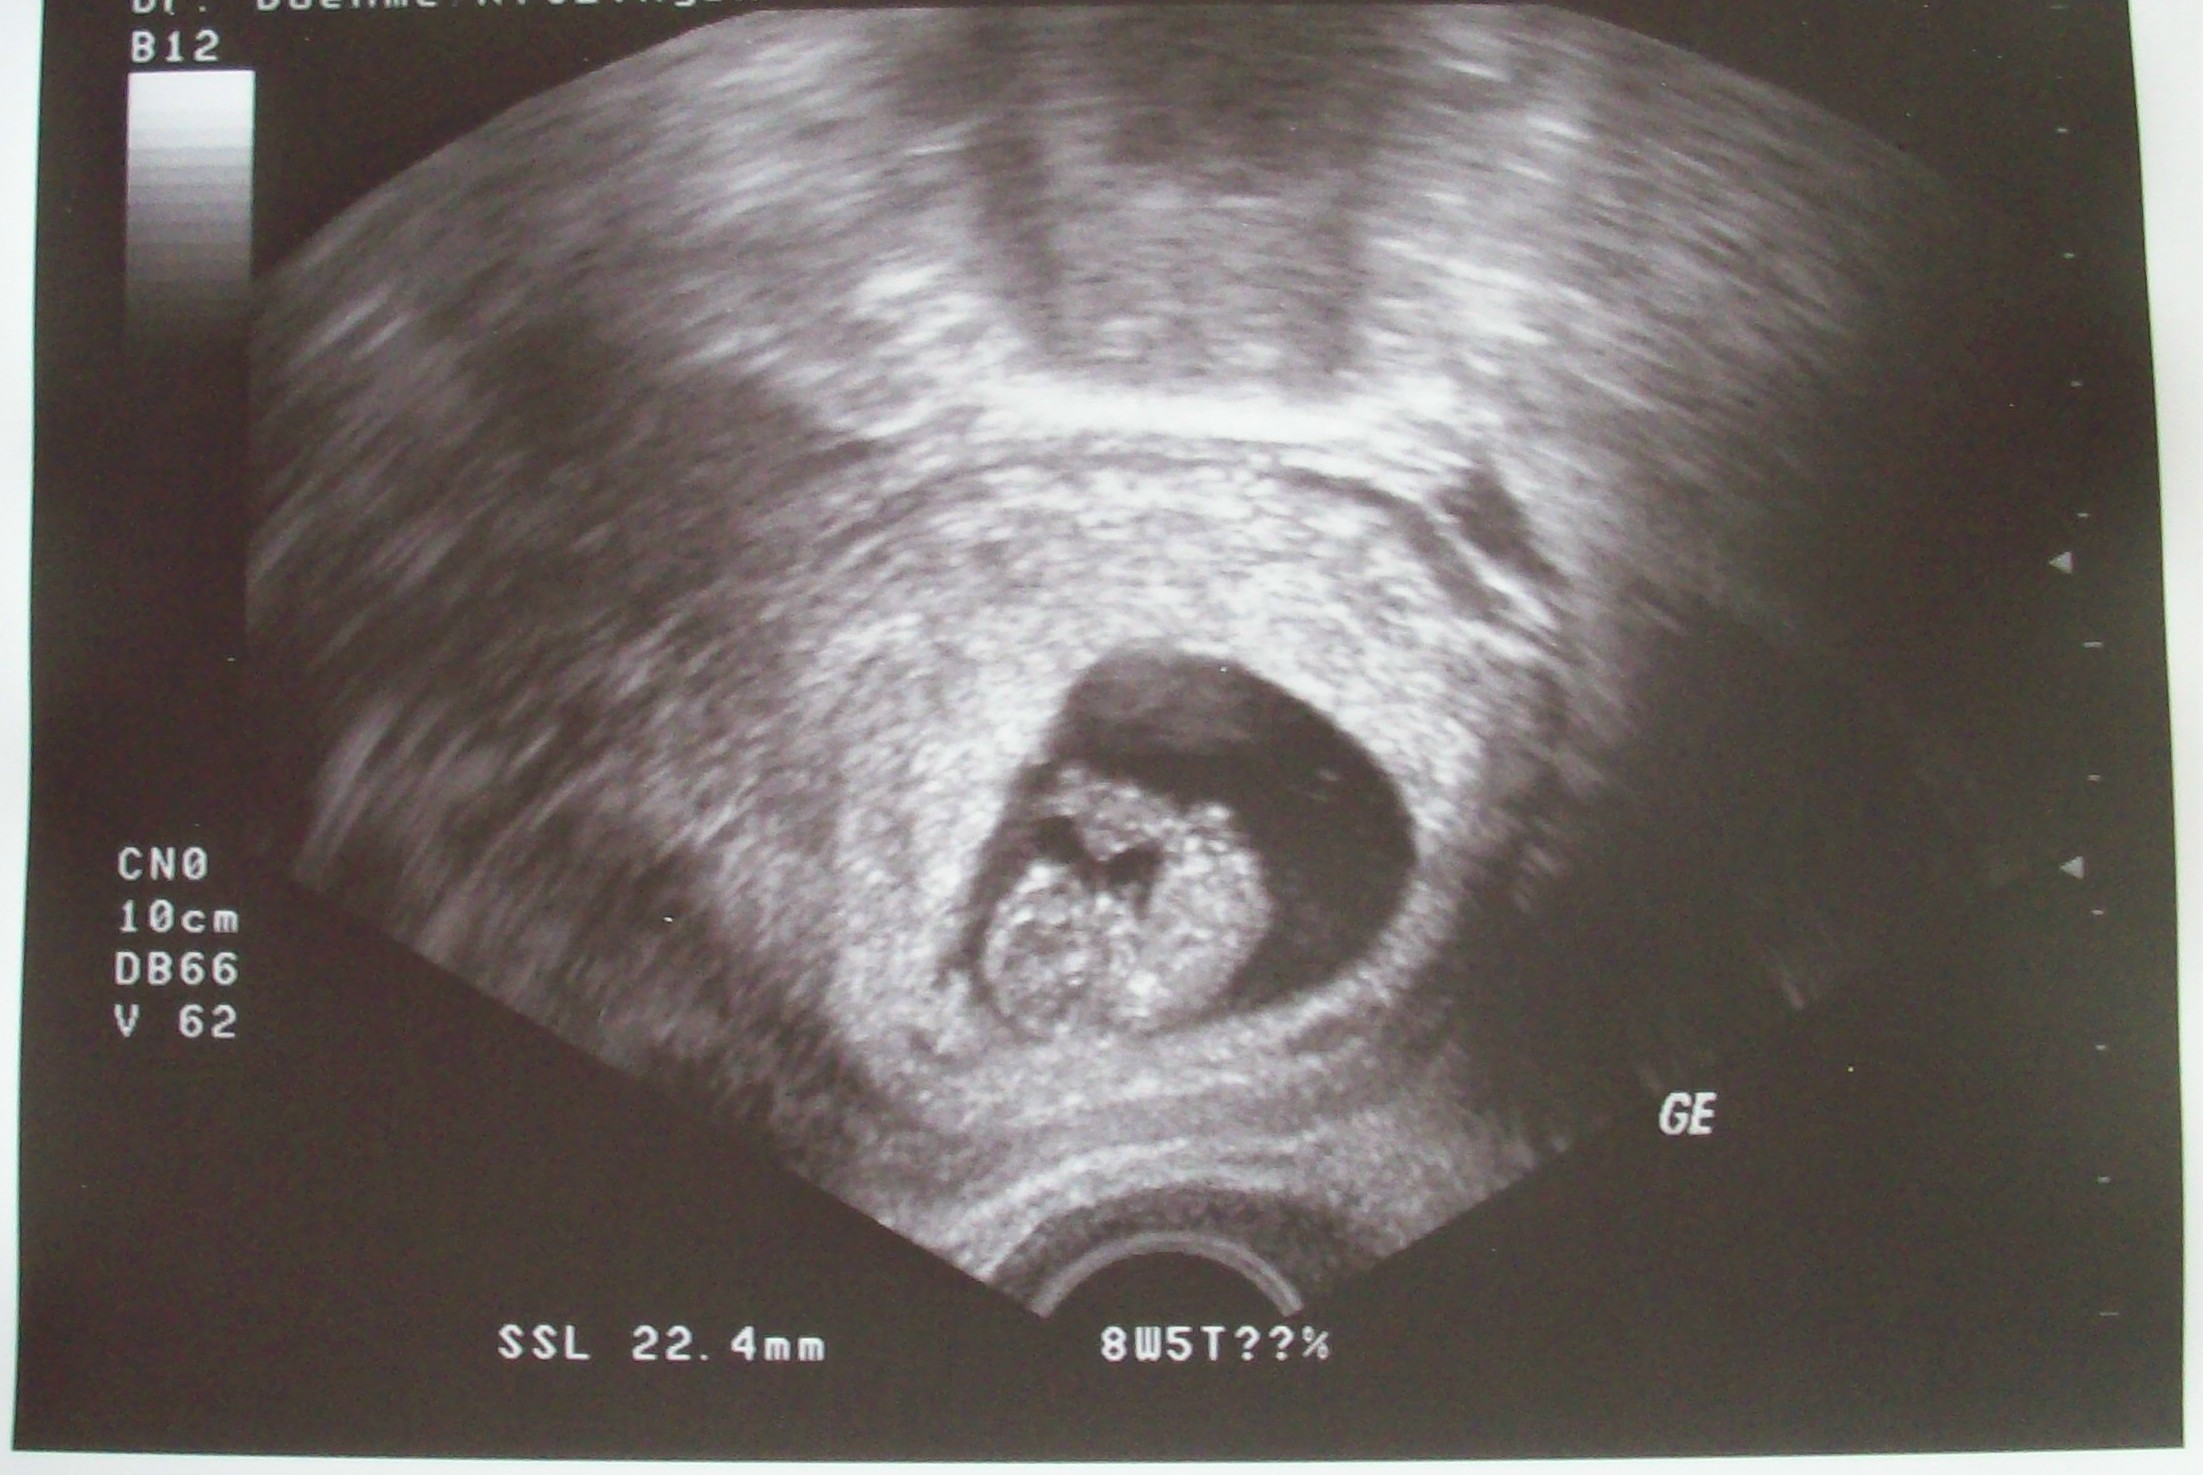

Mensch Bikerin, toll mit dem Bildchen

und super, dass alles ok ist mit eurem Krümelchen